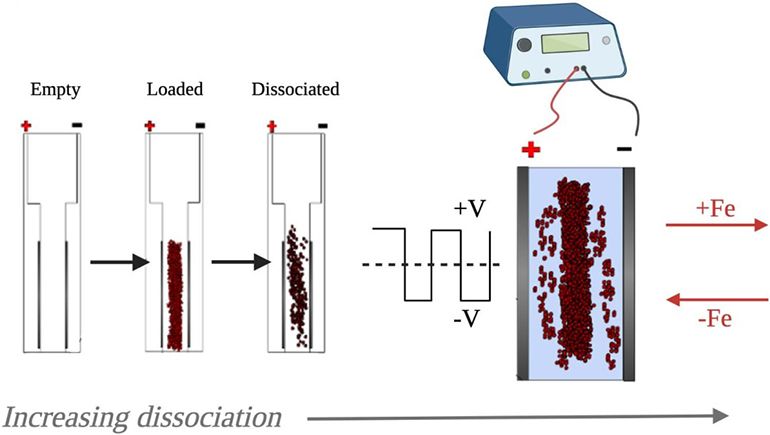

Un equipo de científicos de la Universidad de Brown (Estados Unidos) ha desarrollado una técnica que les permite disociar rápidamente una muestra de tejido en células individuales. El enfoque consiste en colocar una muestra de tejido, como una biopsia de tumor, entre dos electrodos. Luego, las fluctuaciones del campo eléctrico ayudan a tirar de las células en direcciones alternas, lo que eventualmente culmina en su disociación.

Los enfoques actuales suelen implicar el uso de enzimas para digerir muestras de tejido a granel, lo que lleva más tiempo y es más complejo. La técnica será muy útil para los análisis de células individuales, como los análisis genéticos realizados en muestras de tumores para el diagnóstico y la planificación del tratamiento.

La evaluación de las características genéticas de un tumor suele ser crucial para elegir el tratamiento más adecuado y evaluar el pronóstico. Sin embargo, los métodos actuales suelen implicar el uso de enzimas para digerir una muestra de tumor a granel que contiene muchas células y luego realizar un análisis genético en la sopa de letras resultante.

Esto conduce a una falta de especificidad y a un mayor ruido en los datos, lo que puede oscurecer los tipos de células raras dentro del tumor e incluso conducir a un diagnóstico o elección de tratamiento incorrectos. Aislar células individuales de un tumor y luego analizarlas individualmente podría generar mejores resultados, pero es difícil separar las células entre sí. En este contexto, estos investigadores han desarrollado un dispositivo que ayudará.

La tecnología implica el uso de campos eléctricos fluctuantes para separar suavemente las células y necesita tan solo cinco minutos, que es más rápido que los métodos existentes para disociar tejidos, como los que usan enzimas o técnicas mecánicas. Sorprendentemente, las células disociadas no solo son adecuadas para el análisis genético, sino que sobreviven al proceso relativamente ilesas y viables, lo que sugiere que el enfoque puede prestarse a varios enfoques de investigación que requieren una suspensión de una sola célula y luego un cultivo celular adicional.